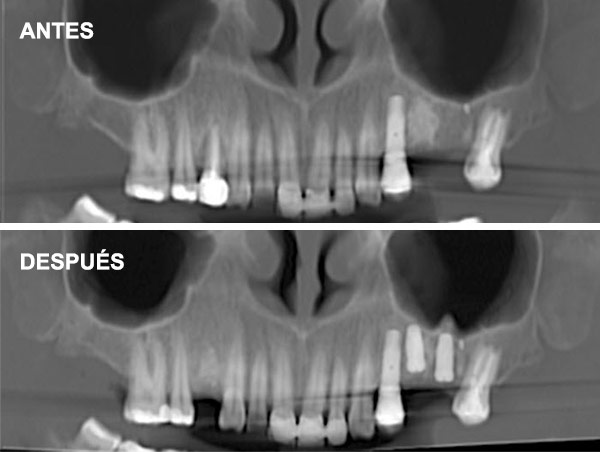

Esta técnica consiste en aumentar la altura y anchura del hueso en los maxilares introduciéndonos en el seno para conseguir una base ósea que permita la colocación de implantes.

Cuando no hay hueso ni distancia suficiente entre el maxilar superior y el seno (altura menor a 5 mm) que imposibilita la colocación de implantes.

Se coloca una membrana y un injerto de hueso liofilizado, un compuesto de procedencia bovina que actúa como osteoinductor (Bio-Oss), así una vez colocado induce al hueso a formar nuevas células. Lo que se intenta hoy en día es encontrar una buena calidad de injerto para acortar el período de formación de hueso. También se coloca una membrana sobre este injerto.

Se realiza a través de una apertura lateral en la pared del seno maxilar (ventana lateral). Este enfoque permite un acceso directo a la membrana sinusal para su elevación.

Indicaciones: Se emplea en casos donde la cantidad de hueso residual es muy escasa (<5 mm) o cuando se necesita un aumento significativo del volumen óseo.